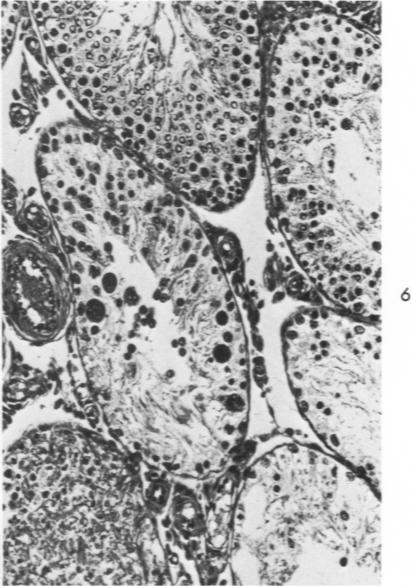

Allergic inflammation, infarction and induced localization in the testis.

Am J Pathol. 1970 Jun;59(3):437-51.

PMID:5424148

原文链接:https://pmc.ncbi.nlm.nih.gov/articles/PMC2032946/